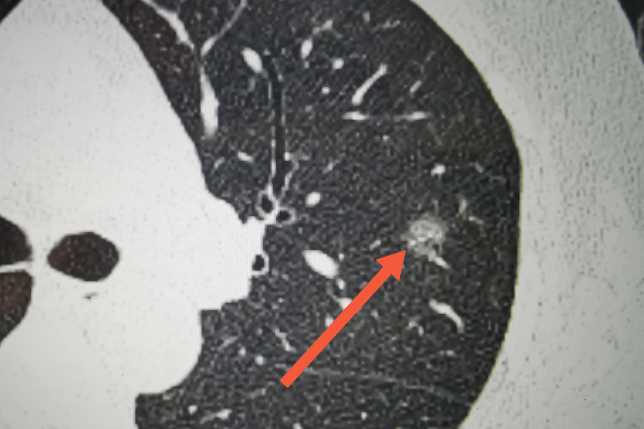

评估肺结节良恶性的第一重要维度并不是大小,也不是形态,而是密度。在这个维度里,肺结节被分为瓷实的实性结节(大哥),柔软的纯磨玻璃结节(小妹)和处于两者之间的混杂磨玻璃结节(二哥)。

这三兄妹能大致反映出肺癌侵袭的不同程度:小妹纯磨玻璃结节一般是癌前病变的不典型腺瘤样增生,瓷实的大哥实性结节如果是肺癌,基本已发展成为浸润性腺癌,二哥混杂磨玻璃则处于微浸润腺癌。

小妹纯磨玻璃结节多表现出惰性行为,可能5年甚至10年都不会有变化;大哥实性结节有50%的可能为良性结节;二哥混杂磨玻璃结节就没这么简单了,如果在纯磨玻璃结节的基础上出现实性成分,那就表明恶性肿瘤细胞已经开始行动了,在逐步侵袭周围正常肺组织。

所以,20mm内同等大小的肺小结节,恶性程度最高的是二哥混杂磨玻璃结节,然后是小妹纯磨玻璃结节,最后才是大哥实性结节。